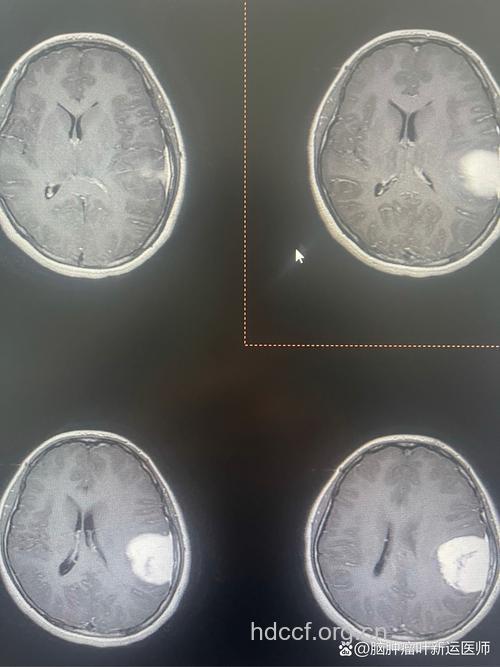

什么是脑肿瘤

脑肿瘤分为良性和恶性两种,约各占一半。恶性肿瘤包括胶质瘤、转移瘤等;良性肿瘤包括脑膜瘤、垂体瘤、神经鞘瘤等。根据肿瘤的来源可分为原发性和继发性两大类。脑肿瘤中发病率最高的是神经上皮性肿瘤,又称胶质瘤,约占40%,其次是脑膜瘤和垂体瘤。尤其值得注意的是,脑转移瘤的发病率正在悄悄增加,有的地区统计发病率已经超过了垂体瘤。